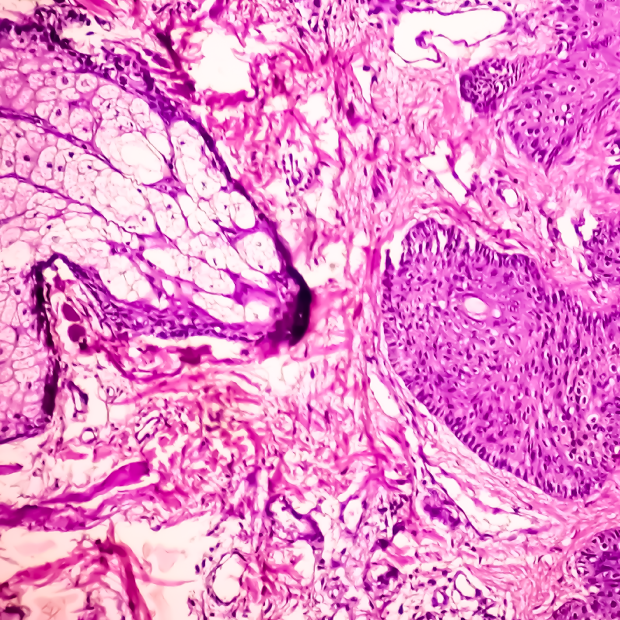

性傳染病(Sexually transmitted infections; STI)是藉由性行為傳染多種疾病的總稱,有超過30種以上的細菌、病毒或是寄生生物可能造成性傳染病,例如披衣菌、梅毒螺旋體、滴蟲、人類乳突瘤病毒(HPV,可能導致尖形濕疣)、人類免疫缺乏病毒(HIV,可能導致愛滋病)等,可能造成生殖器外觀病變、增加罹癌機率、發生免疫不全的症狀、致畸胎性或是垂直傳染給胎兒。根據2017年疾病管制署的統計,罹病人數前5大法定傳染病分別是梅毒、結核病、淋病、HIV感染、後天免疫缺乏症候群,性傳染病就包含了四項,此外,肝炎病毒也會藉由性行為傳播。